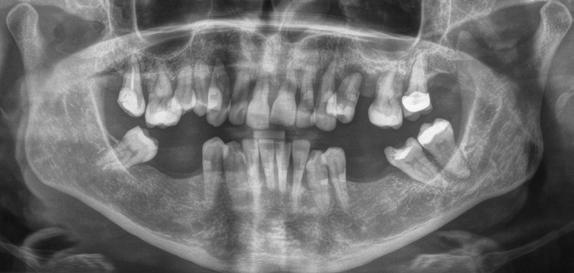

Az 50 éves nőpáciens az alsó és felső állcsont területén egyaránt panaszt (fájdalom, ráharapási érzékenység) okozó, harmadfokban mozgatható fogak miatt jelentkezett rendelőnkben. Az általános anamnézisben említést érdemlő betegség, műtét nem szerepelt. Az elvégzett klinikai és radiológiai vizsgálatok (1–2. ábra) alapján fogai reménytelen parodontális státusúnak bizonyultak, hosszú távon sem megtartásuk, sem protetikai célú felhasználásuk nem volt lehetséges. A parodontális prognózis a fogak eltávolításának abszolút indikációját jelentette. Ezáltal mindkét állcsontban teljes foghiány kialakulásával kellett számolnunk. A protetikai szemléletű, „visszafelé” tervezés elveit követtük a hosszú távú funkcionális, esztétikai siker és szöveti stabilitás elérése érdekében: mindkét állcsontban overdenture típusú fogpótlás készítése mellett döntöttünk. A megfelelő implant-protetikai rehabilitáció alapja az implantátumok megfelelő pozicionálása. A korábbi parodontális kórfolyamat következtében a processus alveolarisokat érintő eredendő csontdeficittel kellett számolnunk, amelyet tovább súlyosbíthatott volna a hagyományos extrakciós technikát követő involúciós atrófia. Ezért a páciens kivizsgálása és megfelelő előkészítése után a fog eltávolításával egy időben PRF

Sticky Tooth segítségével kivitelezett alveolus prezerváció mellett döntöttünk, a megfelelő csontos és mukogingivális gyógyulás minőségi és mennyiségi elősegítése érdekében. A PRF készítmény mennyiségét, minőségét, kezelhetőségét és hatékonyságát jelentősen befolyásolják a páciens laborértékei, ezért kezelési protokollunk szerint a műtétet megelőzően minden esetben laborvizsgálatot végzünk (hemoglobin: 134 g/liter, hematokrit: 0,43, fehérvérsejt: 6,6 G/liter, CRP: 13,60 mg/liter, vércukor: 6,2 mmol/liter, összkoleszterin: 7,00 mmol/liter, triglicerid: 1,08 mmol/liter, HDL koleszterin 2,57 mmol/liter, LDL koleszterin 1,12 mmol/liter), D3 vitamin: 117,5 nmol/liter).

A gyógyulási időszakot követően a csontos gyógyulás ellenőrzése és az implantáció tervezése céljából állcsonti CT-felvételt készítettünk. A CT-felvételen tökéletes csontos gyógyulást észleltünk, az alveoláris csont volumene

teljes mértékben megtartott, a vertikális augmentáció a tervezettnek megfelelő eredményű volt (13–15. ábra), a klinikai kép is ennek megfelelően alakult, optimális menynyiségű keratinizált ínnyel és azt adekvát sebészi technika eredményeképpen megtartott vesztibulummal (16–17. ábra). Az alsó és felső állcsontba 4-4 darab Bredent COPA Sky implantátumot ültettük, D1-D2 csontminőség mellett,